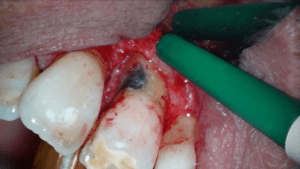

Afbeeldingen 1 (2) t/m 10(2) geven een beeld van element 36 waar wel op tijd de juiste diagnose werd gesteld. De eindfoto’s laten een fraai lateraal kanaal zien dat zorgde voor het interradiculair botverlies en de bijbehorende pocket van 10+ millimeters. Na 6 maanden is het defect volledig genezen.

Flapoperatie

Na anesthesie volgde een flapoperatie om de pocket te openen. Al snel werd een breuk zichtbaar in het element. Maar hoe ver liep de barst door?

Voorzichtig verwijderden we alle granulatieweefsel en spoelden we het schoon. Wat we zagen had ik nog nooit eerder waargenomen. Er zat een min of meer circulaire barst wat eigenlijk een los zittend stukje dentine was.

Na het wegfrezen van het losse stukje vulden we het defect op met composiet. We werken de composiet af met fijne diamantjes en handscalers. Een superscherp geslepen handinstrument kan uitstekend worden gebruikt bij het afwerken van composietvullingen. Wel alleen vlak na het polymeriseren, dan is composiet nog te scalen.

Na polijsten hechtten we de flap en maakten we een afspraak voor een week later.